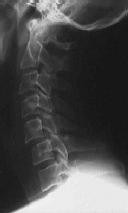

Figures 1 through 3 show the radiograph and CT images of a 68-year-old

woman who sustained a cervical injury after tripping over her cat. She has mild facial trauma, which includes a broken upper incisor and a nonsurgical nasal fracture. She is neurologically intact. Her past medical history is consistent with obstructive sleep apnea, non–insulin-dependent diabetes mellitus (hemoglobin A1c level of 9.0), and morbid obesity, with a body mass index of 40. What is the preferred treatment for this patient?

4. Anterior odontoid screw fixation Discussion: C

Posterior C1-2 fusion with instrumentation provides stability and pain relief with excellent clinical outcomes despite the loss of C1-2 motion. Hard collar immobilization and halo vest immobilization both carry a substantial risk of nonunion in this patient because of her age, fracture displacement, residual fracture gap, and medical condition. Anterior odontoid screw fixation theoretically preserves C1-2 motion. In this case, the fracture is not reduced. Concentric reduction is a requisite for osteosynthesis of the odontoid. Her body habitus also may not allow anterior odontoid fixation.